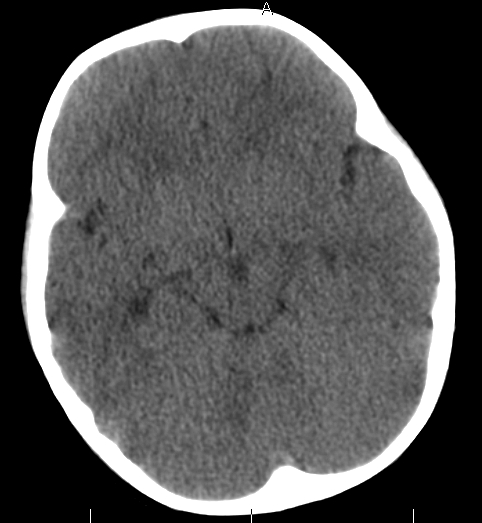

女,3岁,头部外伤一小时。半卵圆中心低密度是什么意思,病灶?侧脑室?请指教。

正常表现

脑白质

考虑为低密度病灶!建议增强或核磁!

幼儿正常脑白质表现,长期观察,必要时mr

从层面看不是侧脑室,考虑低密度变,建议mri。

不是侧脑室,考虑正常脑白质。为慎重,建议mr!